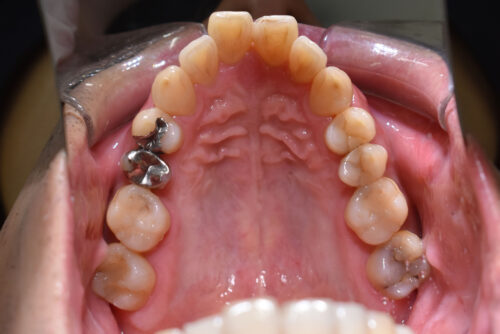

ワイヤー9か月後です。

ワイヤー期間 9か月, 14回来院

本症例も

上顎左右臼歯部に

歯科矯正用アンカースクリュー(デュアル・トップオートスクリュー)を用い

下あごを オートローテーションさせ

また 上下の歯列全体を

後方へ移動させることで

歯を抜かなくても

口元の改善も行いました。

また、下顎の欠損部分は

全てスペースを閉じて

ご自身の歯で

かめるように

矯正治療を終えました。